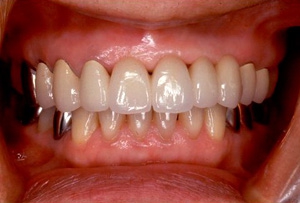

インセラム(オールセラミック)症例①

治療前治療前インセラム(オールセラミック)冠による修復。 主訴は前歯が汚い 金属を使わないオールセラミックでの治療を勧めた。 術前 治療後治療後術後